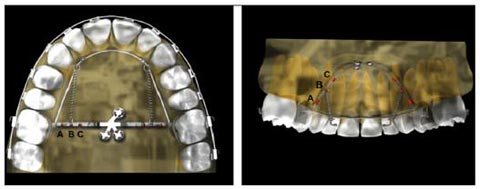

사진=서울성모병원 치과교정과 제공

MCPP는 국 교수팀이 2011년 개발한 교정 치료 장치다. 입천장에 고정하면 돌출된 앞니와 치근이 치아 뒤쪽으로 이동한다. 어금니를 발치하고 헤드기어 등의 구강외 장치나 입안에 복잡한 장치를 장착하는 일반 치아 교정과는 달리, 치아를 발치하지 않아 통증과 상처가 적고, 장치가 입 밖으로 노출되는 불편함이 없다.